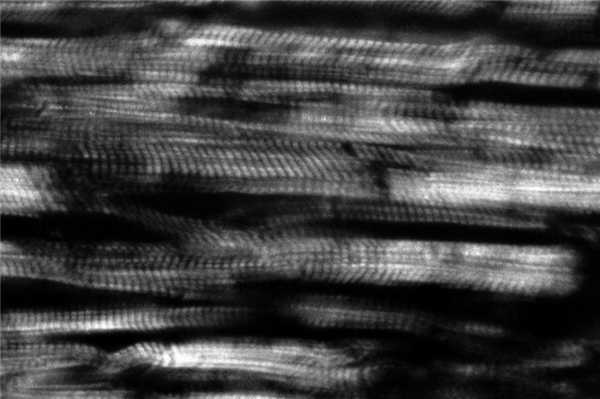

Одной из функций сердца является сократимость — способность сокращаться под влиянием импульсов и выполнять функцию насоса. Элементарной сократительной единицей сердечного мышечного волокна (кардиомиоцит) является саркомер — участок миофибриллы, ограниченный с двух сторон темными линиями, так называемыми Z-линиями. Расстояние между Z-линиями зависит от степени сокращения или растяжения мышц и составляет от 1,6 до 2,2 мкм. Саркомер состоит из равномерно чередующихся светлых — анизотропных (А) и темных — изотропных (I) полос (дисков), придающих волокнам миокарда характерный исчерченный вид (рис. 1). Рисунок 1. Равномерное чередование анизотропных дисков, участки очаговых субсегментарных контрактурных повреждений кардиомиоцитов при ЧМТ с быстрым темпом наступления смерти. Поляризационная микроскопия. Ув. 640. А-диски расположены в центре, образованы толстыми миозиновыми нитями. I-диски состоят из тонких нитей, содержащих актин, тропониновый комплекс (I, T, С), тропомиозин, титин и составляют половину ширины А-дисков [1—6].

У погибших от изолированной черепно-мозговой травмы (ЧМТ), сопровождавшейся быстрым наступлением смерти вследствие повреждения ствола головного мозга, в поляризационной картине преобладает равномерное чередование анизотропных дисков в обоих желудочках сердца (см. рис.1), что соответствует физиологическому строению саркомера. При ЧМТ с непродолжительным премортальным периодом в миокарде левого и правого желудочка превалируют очаговые субсегментарные и сегментарные контрактуры кардиомиоцитов I степени (рис. 2). Рисунок 2. Контрактурные повреждения кардиомиоцитов I степени, очаговые субсегментарные контрактуры, трещины и диссоциация кардиомиоцитов при ЧМТ с переживанием. Поляризационная микроскопия. Ув. 500. Указанные изменения отражают минимальную степень гиперсокращения саркомеров. Независимо от темпа наступления смерти во всех случаях обнаруживали маркеры фибрилляции желудочков сердца, а показатели перикардиальной жидкости (концентрация глюкозы, натрия, калия, кальция и магния) указывали на отсутствие изменения углеводного и минерального обмена в миокарде [32—34]. Следовательно, у погибших по мозговому типу терминального состояния в случаях изолированной ЧМТ независимо от продолжительности премортального периода остановка сердца не связана с потерей сократительной способности миокарда. Она обусловлена нарушением его иннервации со стороны центральной нервной системы (ЦНС) с последующим возникновением фибрилляции желудочков сердца (фибрилляция желудочков центрального генеза).